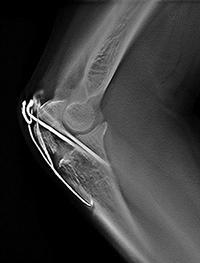

トモシンセシス画像

金属のアーチファクトが低減でき,

骨折など金属固定している部分の

経過観察に有用

3.金属アーチファクトの低減

整形外科領域にて,ボルトやプレートなど金属固定された部位の術後の経過観察を行う場合に,画像診断を困難にしている金属アーチファクトが抑えられるため,骨の癒合状態などの金属周囲の骨評価が容易である。